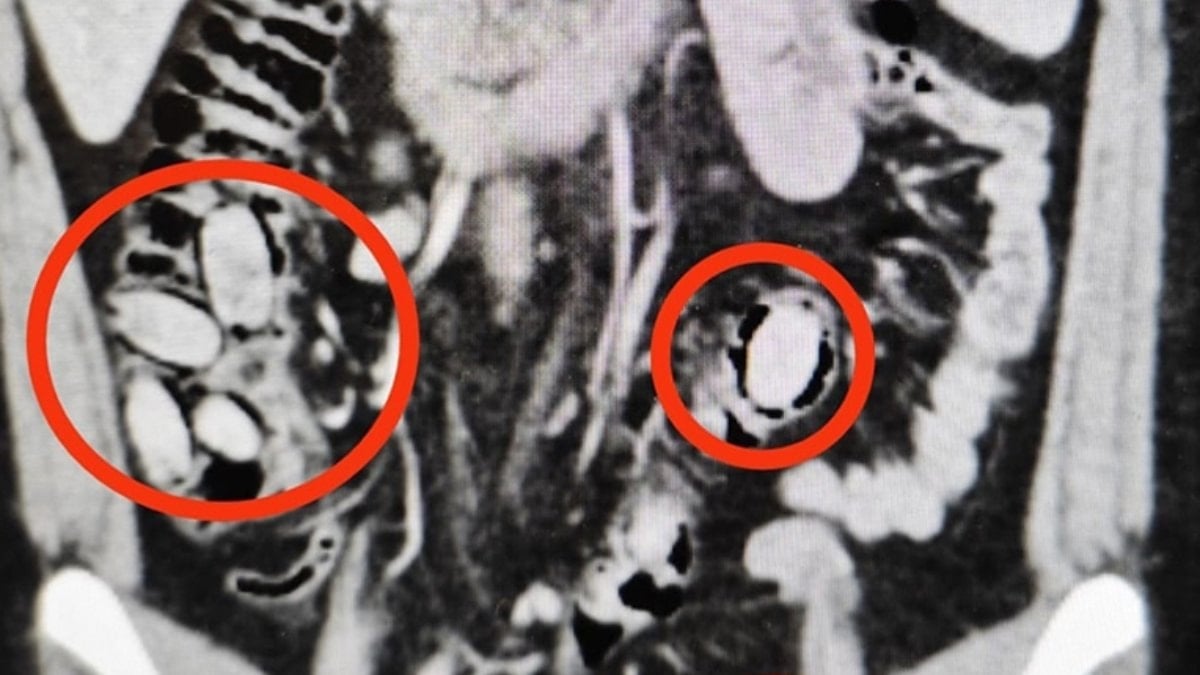

Hastane kontrolüne götürülen 25 yaşındaki S.A.’nın midesinde 44 kapsül sentetik uyuşturucu olduğu belirlendi.

Operasyonla midesindeki kapsüller çıkarılan S.A., hastanedeki tedavisinin ardından sevk edildiği adliyede çıkarıldığı hakimlikçe tutuklandı.